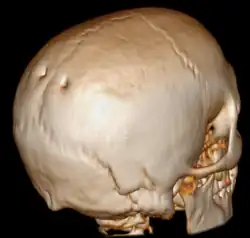

Surface rendered CT of the back of the skull. The parietal foramina are visible at left. | |

A parietal foramen is an opening in the skull for the parietal emissary vein, which drains into the superior sagittal sinus. Occasionally, a small branch of the occipital artery can also pass through it. It is located at the back part of the parietal bone, close to the upper or sagittal border. It is not always present, and its size varies considerably.[1] Parietal foramina tend to be symmetrical, with the same number on each side.[1]